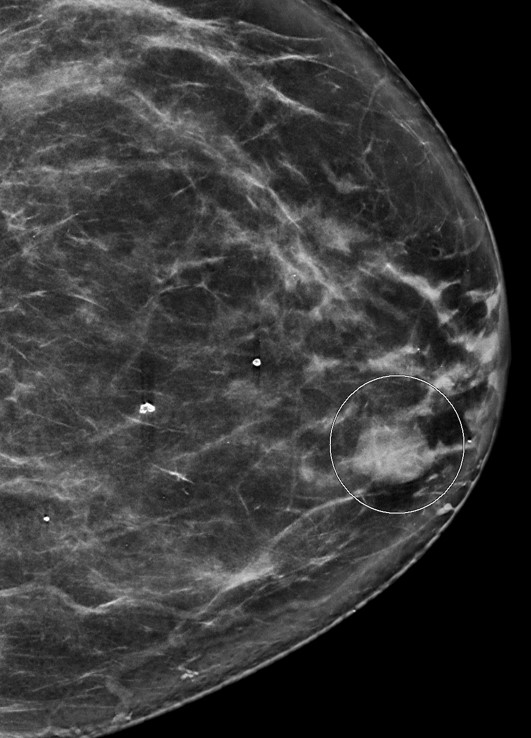

- No distinct imaging findings can distinguish between subtypes of papillary carcinomas (AJR Am J Roentgenol 2012;198:264, Front Surg 2022;8:743881)

- Imaging does not distinguish encapsulated papillary carcinoma (EPC) with and without invasion beyond the capsule (Breast J 2019;25:539, Breast J 2021;27:209)

- Mammography:

- Circumscribed to lobulated, round to oval mass

- May have irregular, angulated or multilobulated borders

- Calcifications uncommon

Radiology images

Contributed by Mariel Molina Nunez, M.D. and Julie Jorns, M.D. (Case #518)

Images hosted on other servers: